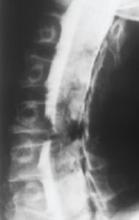

A myelography of the cervical spine of a 59-year-old man with cervical radiculopathy shows C6 nerve root impingement.Epidural steroids appear effective